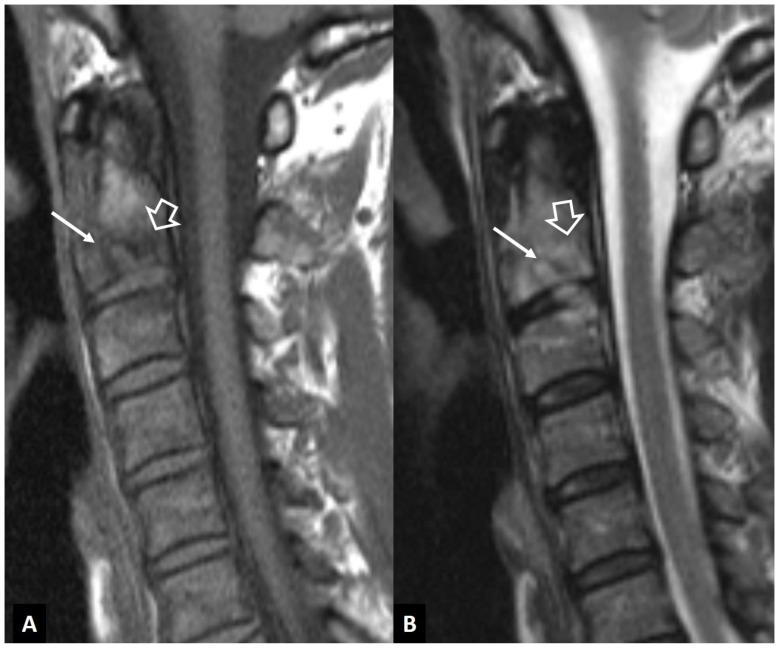

A series of conditions can mimic musculoskeletal infections on imaging, complicating their diagnosis and affecting the treatment. Depending on the anatomical location, different conditions can manifest with clinical and imaging findings that mimic infections. Herein we present a wide spectrum of the musculoskeletal disorders of the axial skeleton, long bones, peripheral joints, and soft tissue that may manifest as infectious processes, and we focus on the potential mimics of osteomyelitis, septic arthritis, and infectious spondylodiscitis that are common in clinical practice. We present the typical imaging characteristics of each musculoskeletal infection, followed by mimicking conditions.

一系列病症在影像学上可模拟肌肉骨骼感染,使诊断复杂化并影响治疗。根据解剖位置的不同,不同病症可表现出类似感染的临床和影像学表现。在此,我们展示了轴向骨骼、长骨、外周关节和软组织的广泛肌肉骨骼疾病,这些疾病可能表现为感染过程,并且我们重点关注临床实践中常见的骨髓炎、化脓性关节炎和感染性脊椎间盘炎的潜在模仿病症。我们介绍了每种肌肉骨骼感染的典型影像学特征,随后是模仿病症。